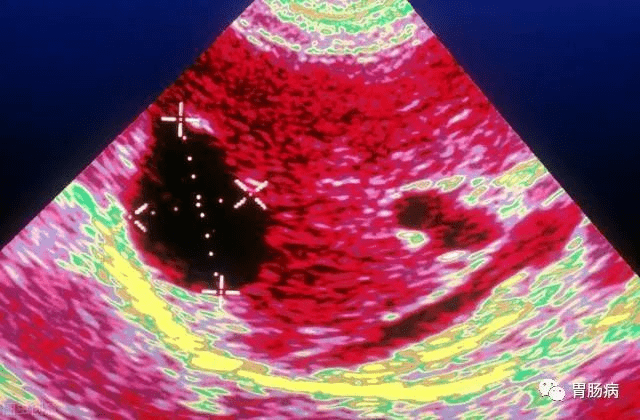

超声是最有效的初检手段 , 如果需要进一步鉴别 , 可以再做CT或者核磁共振 , 甚至穿刺针吸活检等检查 。

最常见的单纯性肝囊肿 , 在超声检查中表现为肝脏内部出现的澄清液体的囊性结构 , 偶然体检发现的无症状患者不需要对肝囊肿进行治疗 , 单纯性肝囊肿也不需要反复做检查 。